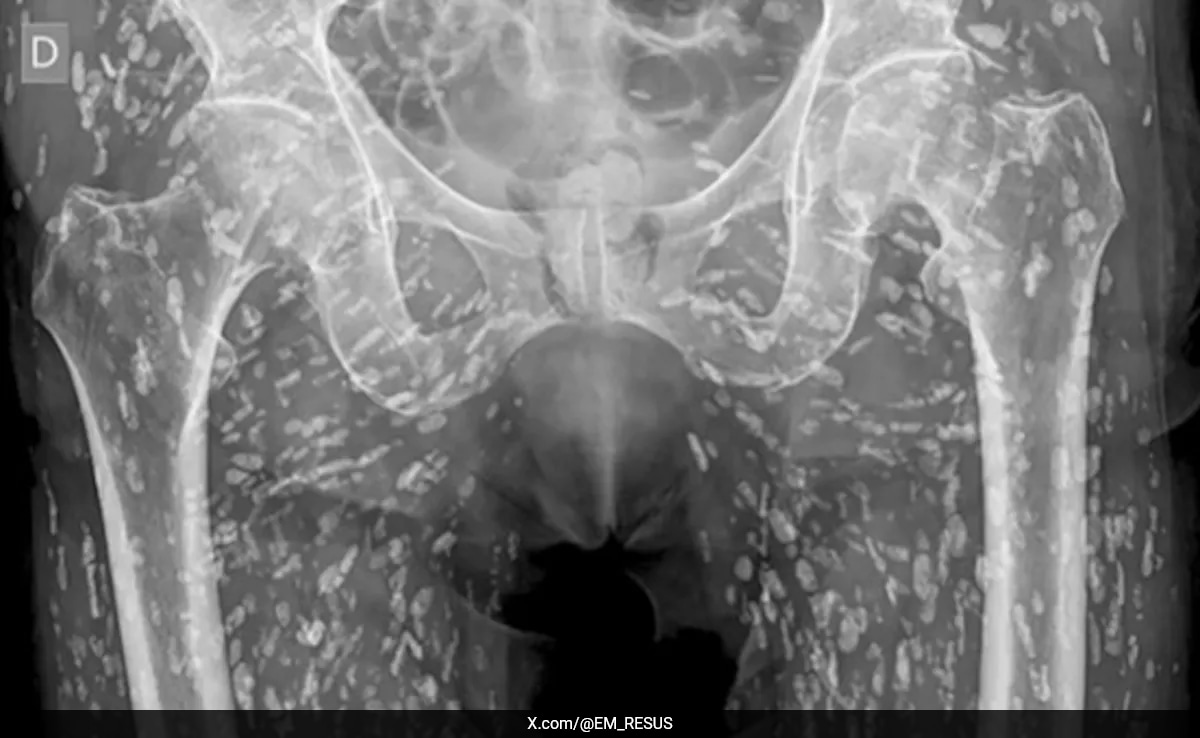

A chilling X-ray scan displaying calcified parasites embedded throughout a patient’s body has gone viral on social media. The image, shared by emergency room doctor Sam Ghali, shows what he described as one of the “most insane X-rays” he’s encountered, with the patient’s torso dotted by countless oblong shapes resembling a hailstorm.

Dr Ghali said that the disease, which is termed cysticercosis, is due to the presence of larval cysts of the tapeworm Taenia solium. The parasite infects humans through eating raw or undercooked pork infested with larval cysts. Though the tapeworm can develop within weeks in the human gut, cysticercosis is caused by the migration of larvae into soft tissues where they eventually calcify and form cysts.

According to a report by The New York Post, cysticercosis materialises when infected people pass on tapeworm eggs to others through their faecal matter. This can happen when people don’t properly wash their hands after using the bathroom or through water contaminated with faeces.

This unnamed patient case makes one appreciate the risks of eating pork that has not been properly cooked, for infections from such could lead to more complicated conditions like muscles, skin damage, and even to the brain. This X-ray image is enough to make anyone recall the consequences of bad food preparation.